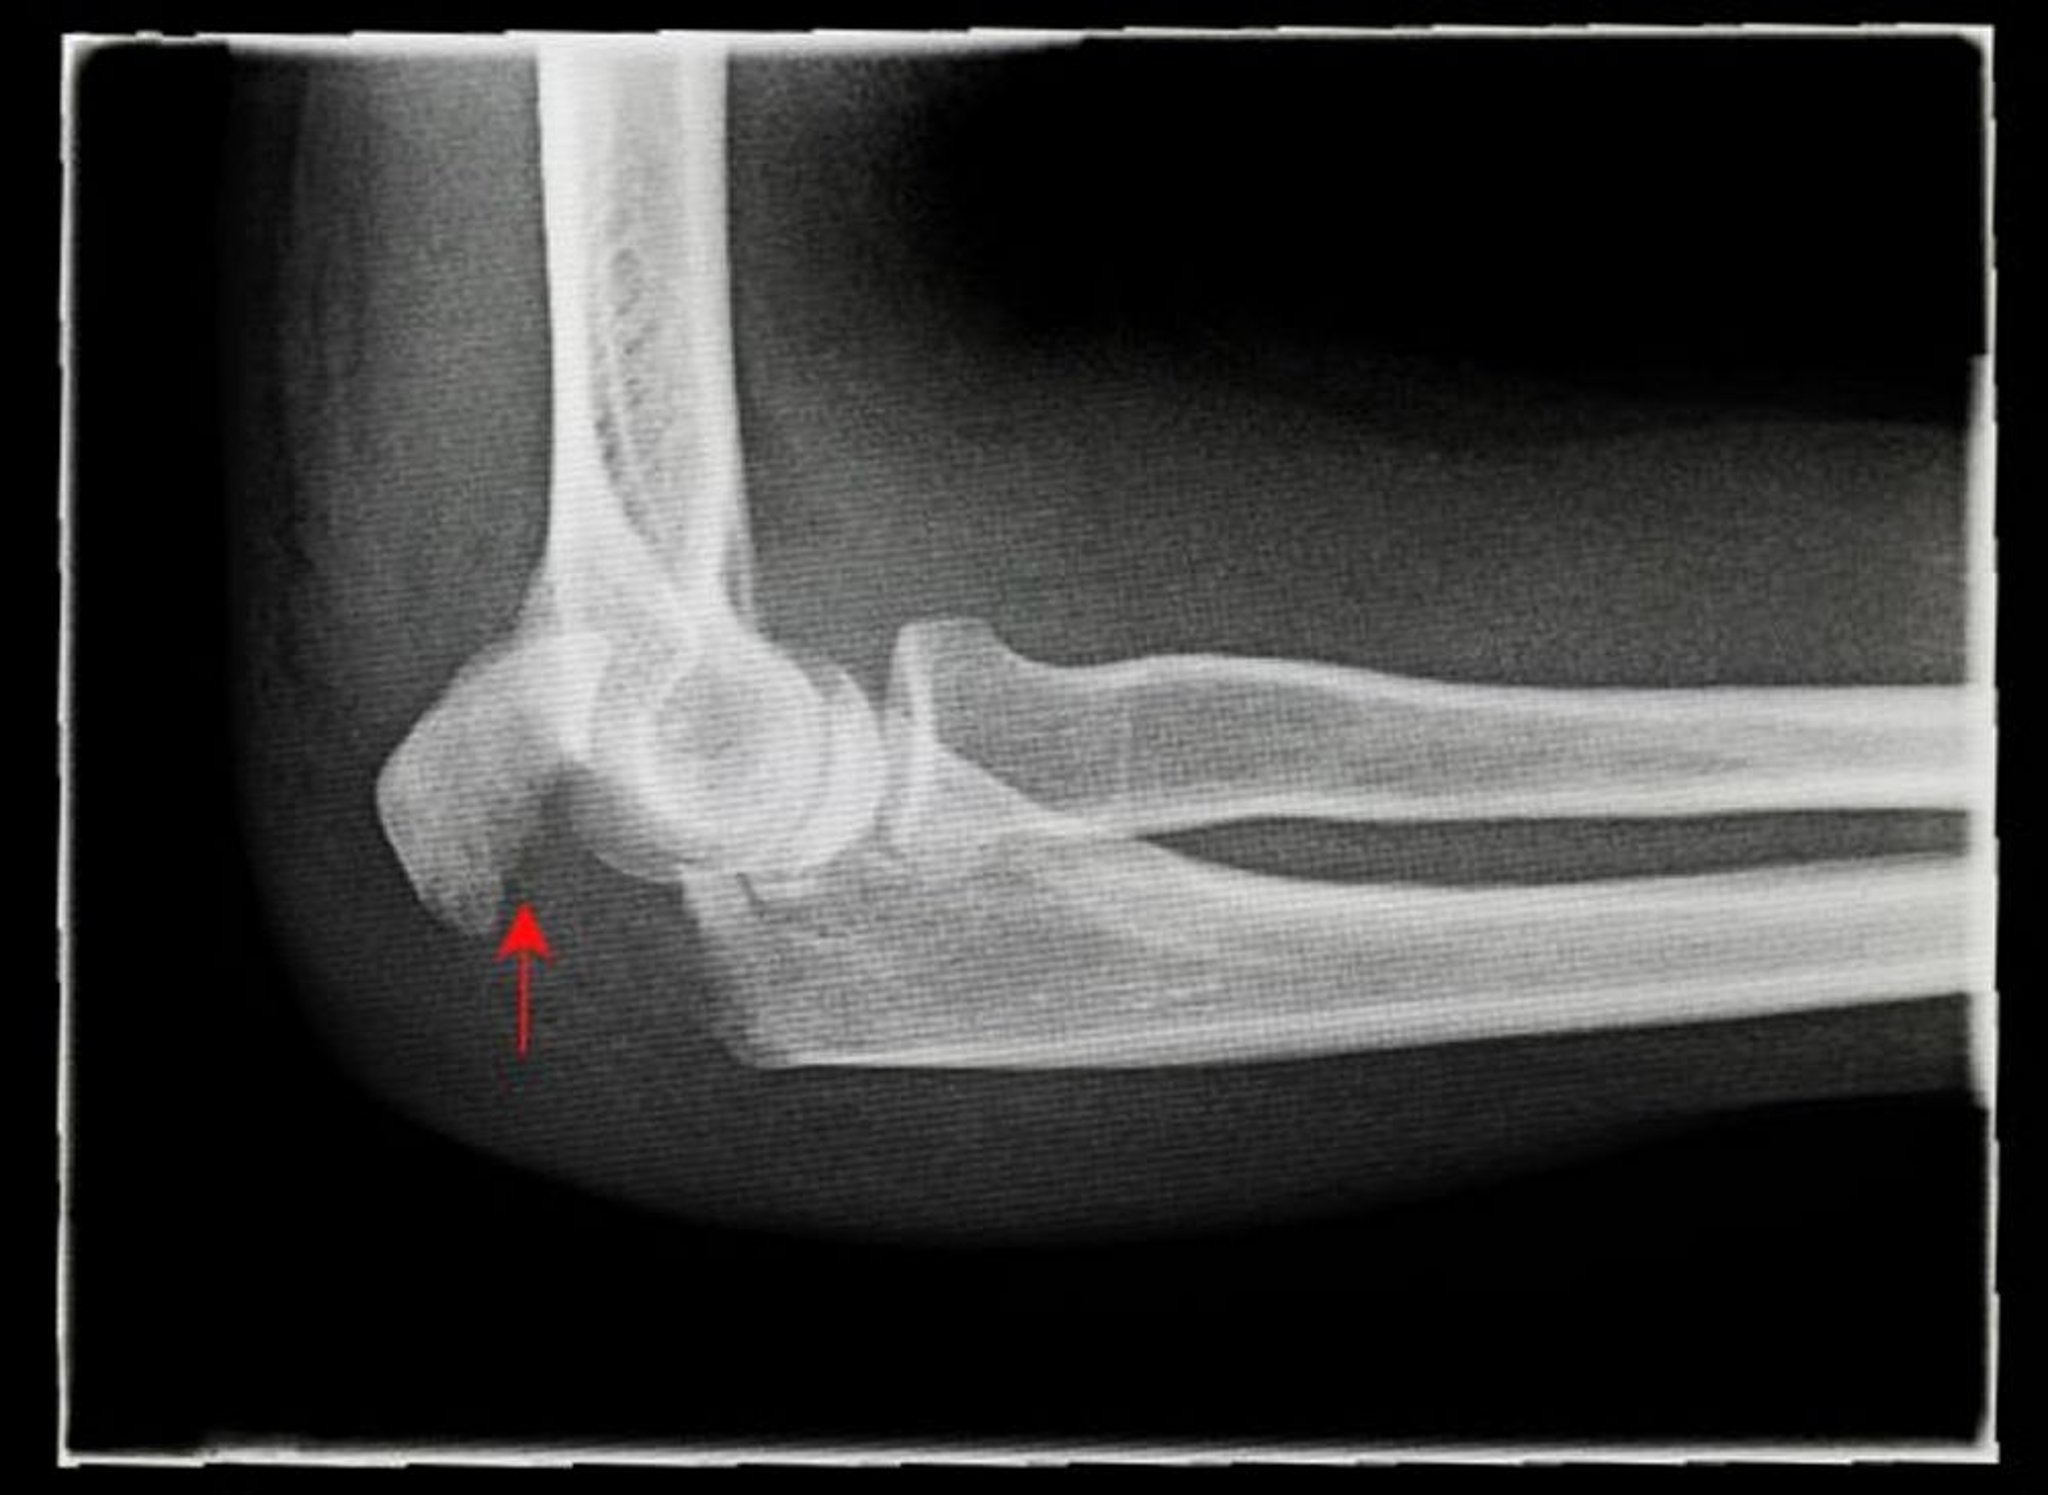

Fratura deslocada do olécrano

Esta radiografia mostra uma visão do lado (lateral) de uma fratura deslocada do olécrano (seta).